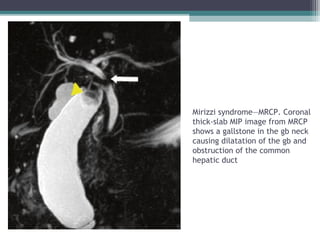

Mirizzi Syndrome

• Complication of long standing Cholelithiasis Charecterised by Common hepatic

duct or CBD obstruction due to extrinsic compression from an impacted gall stone

in cystic duct or gall bladder neck or from associated inflammatory changes .

• HALLMARK FEATURE :

Cholelithiasis with IHBR and Dilated Common Duct till the porta hepatis beyond

which CDB is normal in calibre

Mirizzi syndrome—MRCP. Coronal

thick-slab MIP image from MRCP

shows a gallstone in the gb neck

causing dilatation of the gb and

obstruction of the common

hepatic duct